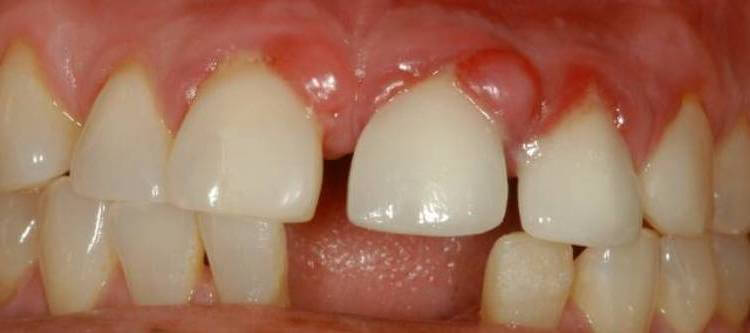

Свищ – это патологическое отверстие (перфорация) в десне. Внешне он выглядит как выпуклое образование размером от 0,3 до 1 см в диаметре, с красной каймой и белым пятнышком посредине. Служит канал для вывода скопившегося под десной гноя.

Проявления свища явные, поэтому его не спутаешь с другими заболеваниями. Главный признак – патологическое отверстие в десне, через которое выделяется гнойное содержимое с примесью крови или без нее.

Как выглядит свищ на десне у взрослого? Это небольшое образование округлой формы, красноватого или белесого оттенка, напоминающее прыщ или «шишку» с отверстием в центре или без него (в фазе созревания). Сопутствующие признаки при этом будут следующими:

Ответ на вопрос, что такое свищ в зубе, прост. Это своеобразный канал, служащий для вывода гноя из инфекционного образования в челюсти. При осмотре в зеркале или на фото он выглядит как прыщ или чирей (фурункул): на десне появляется выпуклое округлое образование с красной каймой и белой точкой внутри (отверстием), через которую вытекает экссудат.